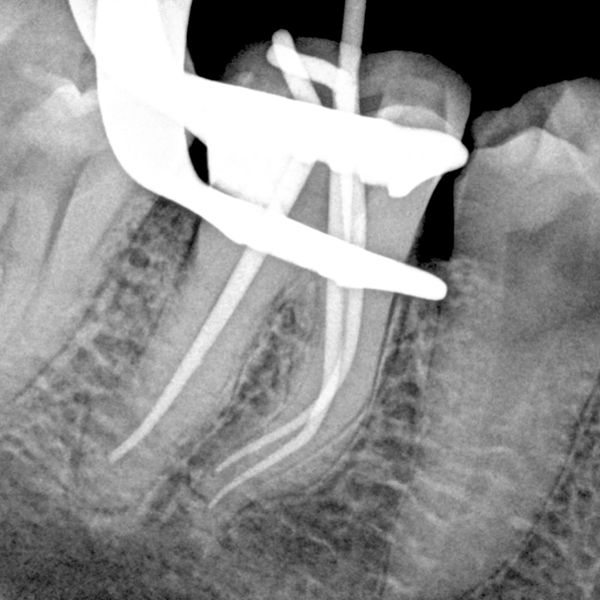

Engage in interactive clinical systems that mirror real endodontic cases, preparing you for practice-ready challenges.

Deep-dive video content covering every facet of root canal treatment—clarify techniques and advance your skills at your own pace.